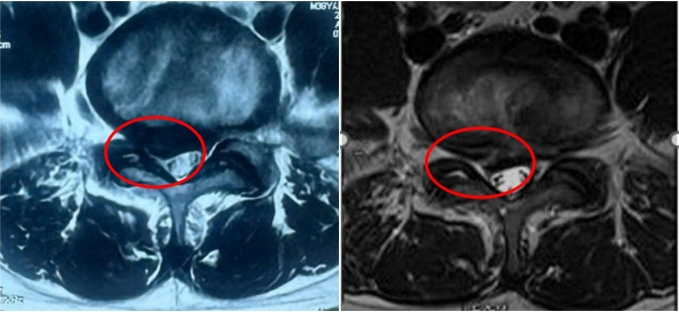

Kết quả chụp cho thấy phần thoát vị co lại sau đốt sóng cao tần. Ảnh: Bệnh viện Đa khoa Tâm Anh

Khối thoát vị (bên phải) sau khi đốt sóng cao tần co lại so với trước khi can thiệp (bên trái). Ảnh: Bệnh viện Đa khoa Tâm Anh

Sau tháng đầu tiên can thiệp, các cơn đau giảm, từ tháng thứ 2, thứ 3, cơn đau gần như không còn, anh Hiếu có thể đi lại bình thường. Tái khám sau ba tháng can thiệp, khối thoát vị đã co hồi được một phần, không còn hình ảnh chèn ép rễ thần kinh rõ rệt.